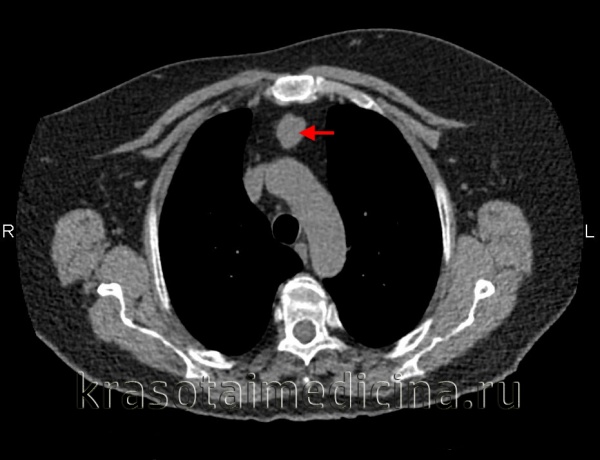

Больная П., 38 лет, поступила 31/VIII 1994 г. с диагнозом: опухоль средостения. Жалобы на тупые боли и чувство онемения в левой половине грудной клетки, одышку, слабость, повышенную потливость. Больна в течение года, симптомы болезни усиливаются.

При обследовании в клинике со стороны сердечно-сосудистой системы легких отклонений не найдено. На рентгенограммах видна овальной формы тень, расположенная справа в передневерхнем средостении. После искусственного пневмоторакса установлена интактность легкого. Заключение: киста передневерхнего средостения.

6/Х операция. Под местной анестезией передним доступом через третье межреберье справа вскрыта плевральная полость. В передневерхнем отделе средостения обнаружена опухоль размером 12 х 10 см, мягко-эластической консистенции, спаянная с верхней полой и непарной венами. При мобилизации опухоли вскрыта ее полость, из которой удалено около 100 мл жидкости, имевшей вид молока. Опухоль с капсулой удалена. Послеоперационное течение гладкое.

Гистологическое исследование показало налииче кистозной лимфангиомы. Видна стенка кисты, состоящая из волокнистой соединительной ткани, сосуды полнокровны. Определяются лимфатические фолликулы, мелкие лимфатические узелки, участки жировой ткани.